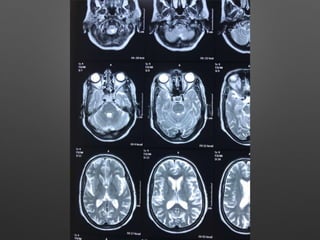

HOPI • Patient wasapparently normal till 5pm 3/2/18, started behaving abnormally like half dressed, with carrying comb and want to go temple, with irrelevant talks. • Relatives observed paucity of left Upper and lower limb, thinking of stroke - took her to near by hospital • Asked for imaging - after imaging she developed 2 episodes of left sided jerky movements of both UL & LL with twitching over the face - lasted for 1-2 min, treated with sedative , Inj. insulin for high CBG - 495 mg/dl and referred here for further management.

Provisional Diagnosis • ?Acuteischemic stroke - left hemiparesis with focal seizures • ? Hyperglycemic encephalopathy • ? Viral encephalitis

Investigations • HB- 14.1gm%- 12.2 • WBC- 15990cells/cumm - 10770, -P 83%, L-9%,M-7% • Platelets - 3.3lakhs - 2.8 • ESR- 63mm/hr • RBS - 267 mg/dl • CUE - N • RFT - N • LFT - N • S.Na - 137, k+ - 3.9, Mg- 2.1, Ca- 9.1, Ph- 3.5, Ammonia- 0.29

• ECG -N • 2DEcho- N • U/S - Abd- Gr I Fatty liver changes

Final Diagnosis • ?Acute stroke • ? Viral Encephalitis • ? Hyperglycemic encephalopathy